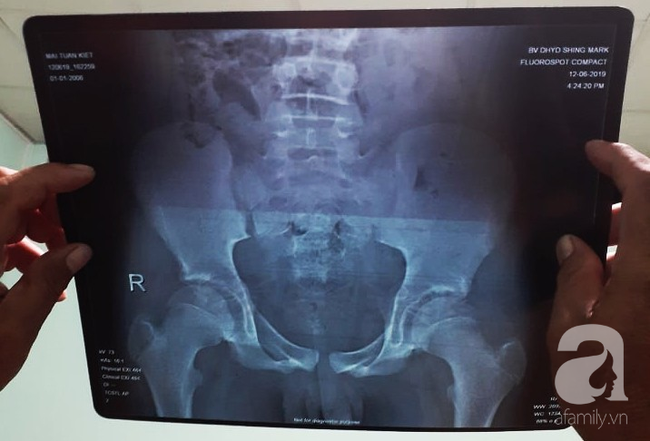

Ảnh chụp X-quang của bé K.

Sau khi xem các chẩn đoán lâm sàng và phim chụp X-Quang, vị bác sĩ khẳng định chắc chắn bệnh nhi này có tổn thương gãy xương.

"Nói bé bị viêm ruột thừa là chống chế, vì viêm ruột thừa sau chấn thương khung chậu là vô cùng hy hữu. Khả năng cao là bé đã gãy xương và bị thủng tạng rỗng gây nhiễm trùng viêm phúc mạc. Xét nghiệm lâm sàng có giá trị trong trường hợp này là siêu âm và chụp CT.

Đây là ca tương đối phức tạp, vì trẻ em còn sụn tăng trưởng ở các đầu xương gần các khớp xương. Do đó nếu không phải bác sĩ chuyên khoa chỉnh hình có kinh nghiệm thì nhìn phim X-Quang rất khó nhận ra tổn thương khung chậu" – bác sĩ phân tích.